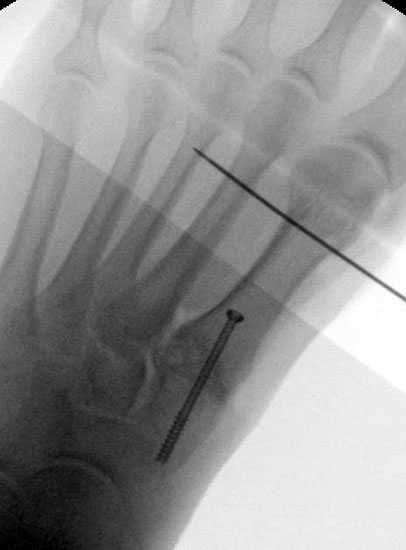

Röntgenaufnahme des Fußes im Stehen im dorsoplantaren und seitlichen Strahlengang (Abb. 1a-b).

Beurteilung des ersten Intermetatarsalwinkels (IMA), des Hallux valgus Winkels (HVA), des distalen (Distal Metatarsal Articular Angle, DMAA) und proximalen Gelenkflächenwinkels der Grundphalanx (Proximal Phalangeal Articular Angle, PPAA).

Abbildung 1a

Abbildung 1b